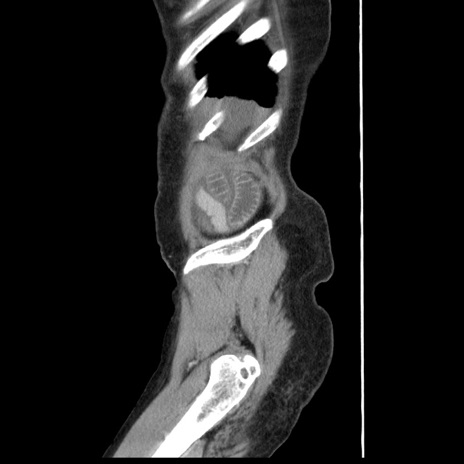

横断像